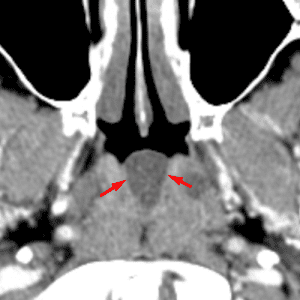

Tornwaldt Cyst

Mimicking a mass